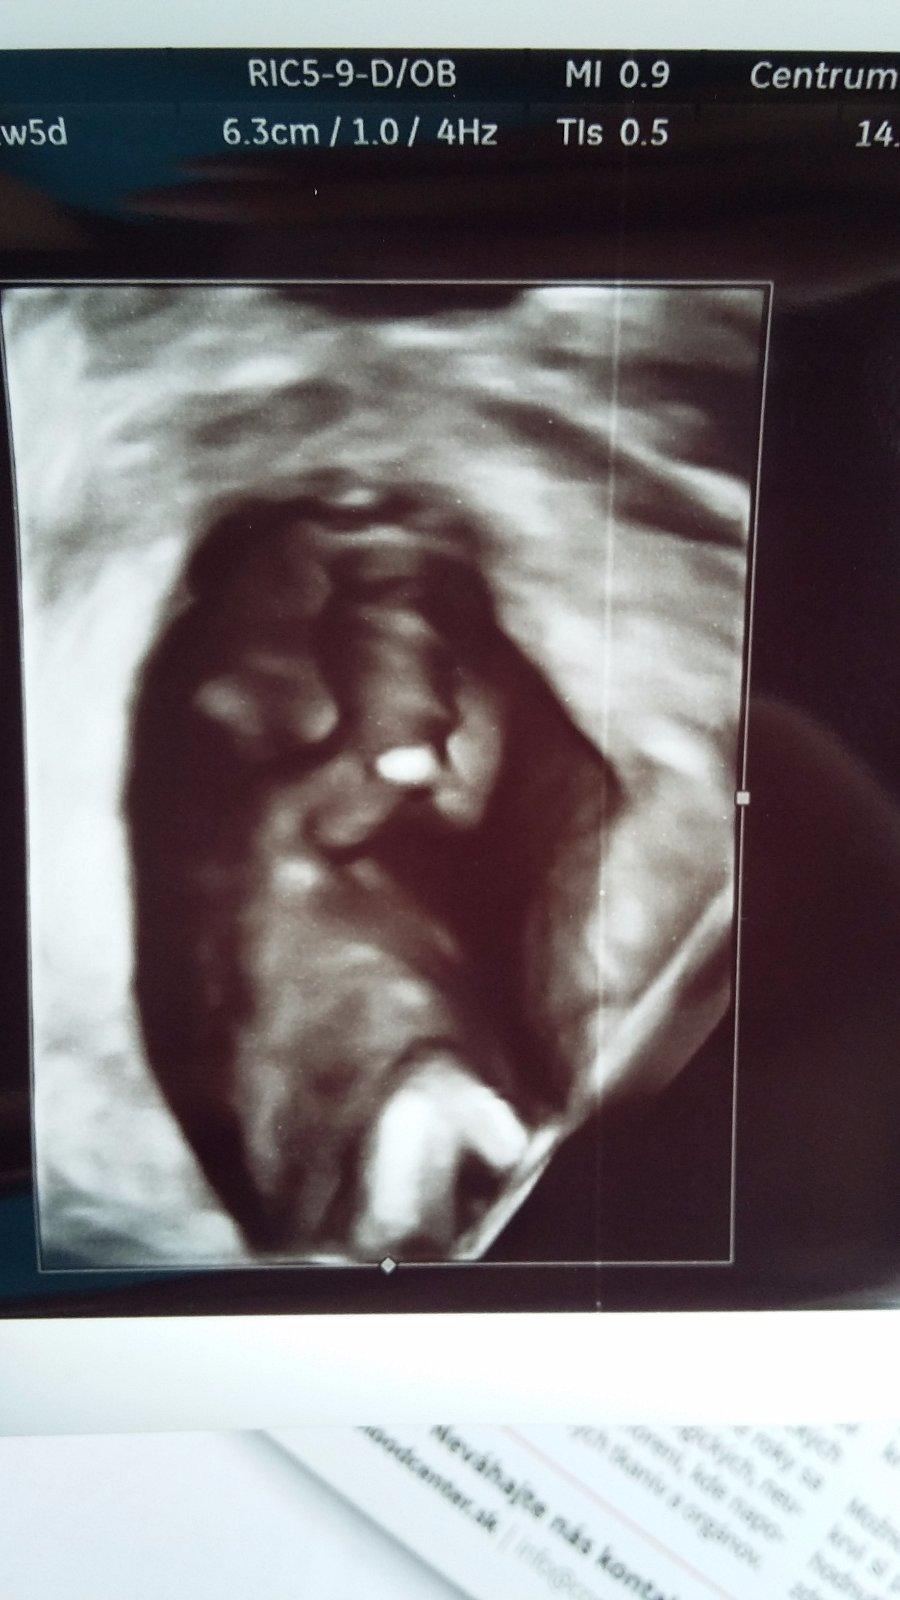

Ahojte baby 🙂 uz mam po poradni 🙂 dopadla super 🙂 vsetko v poriadku . babo o trosku mensie ale ze to je v pohode 🙂 ved velke nechcem kto by to porodil potom 😂 mam aj dve fotky 🙂 dalsia poradna 8.8 🙂 malinke sa riadne vrtelo 🙂 tesime sa 🙂 predpokladany termin 23.1. 🙂